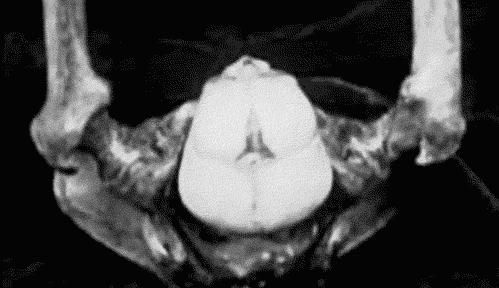

但物种之间会有深入程度的不同,如马、牛等胚胎仅位于子宫内表面,狗和猫则会稍深入一点。

而人类和其他灵长类动物的胎儿,则几乎穿透整个子宫内膜,就像整个沐浴在母亲的血液中。

各种动物胚胎附植示意图